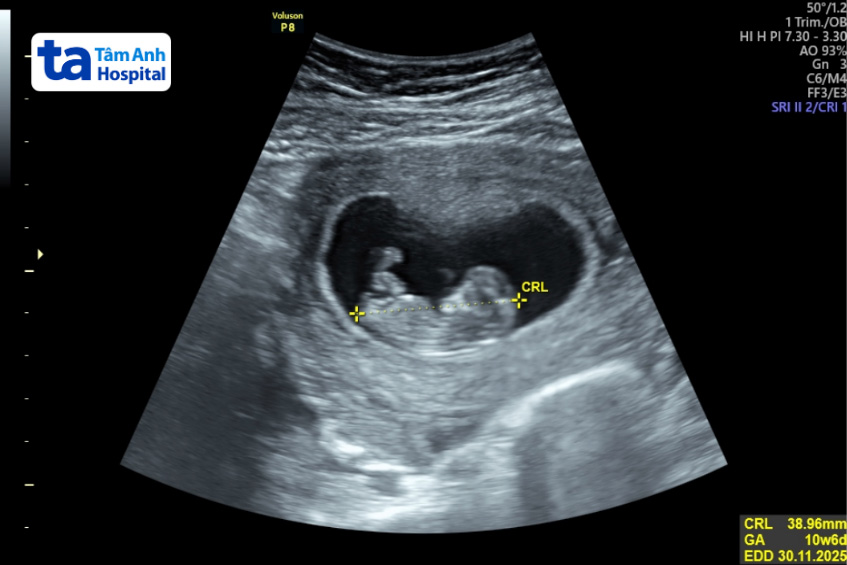

Bên cạnh đó, vợ chồng cần hoạt động thể thao và kiểm soát căng thẳng với những bài tập yoga, thiền định hoặc thả lỏng tâm trí giúp duy trì sự cân bằng hormone, giúp cải thiện khả năng sinh sản. Sau hơn 2 tháng điều trị cũng như tuân thủ theo hướng dẫn của bác sĩ, anh chị đã có thai tự nhiên. Hiện tại thai nhi được hơn 12 tuần, phát triển bình thường.